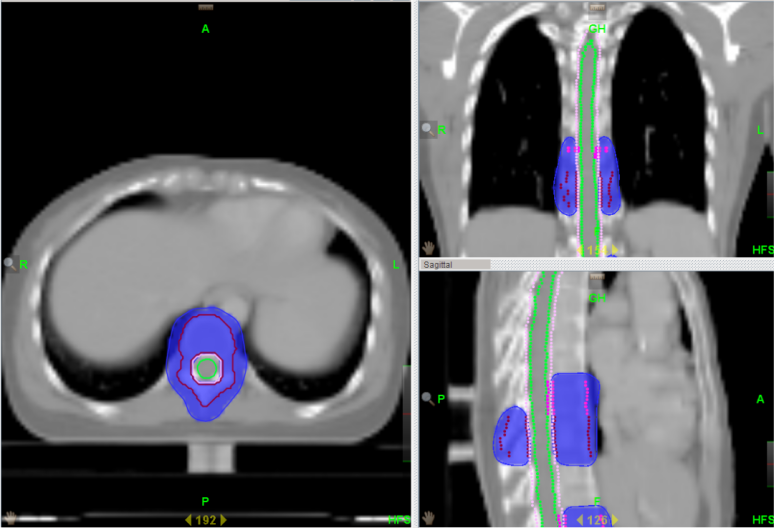

为了让“我”的优点发挥的更加明显,让更多的患者能够在“我”的治疗下得到痊愈。湘南学院附属医院引进的TomoTherapy(简称TOMO)——螺旋断层放疗系统,属于最新一代放射治疗设备。是目前唯一采用放疗照射与CT同源的影像引导放疗系统。成像精度高达±0.1mm,远远高于常规加速器。

与普通的“我”相比,TOMO放疗有以下优势:

1、对全身多发病灶及病变较长的大肿瘤,超出普通加速器治疗所能达到的范围,常规放疗往往不能同时包括,TOMO能够实现连续同时完成照射。包括易通过淋巴转移产生多病灶的恶性肿瘤、全脑全脊髓和全身骨髓调强照射等。

2、对解剖结构复杂等难治性、特殊的恶性肿瘤更具优势。包括鼻咽部肿瘤、全颅骨放疗、头皮恶性肿瘤、胸壁恶性肿瘤等。

3、对紧邻重要脏器或组织的恶性肿瘤,如肿瘤紧邻肝、肾、肺、鼻咽、前列腺等重要器官时,由于这些脏器对射线敏感,往往制约常规放疗放射剂量的提高,TOMO能够避开重要器官,降低副反应的同时提高放射剂量,使得既往不易放疗的患者变为可以放疗。